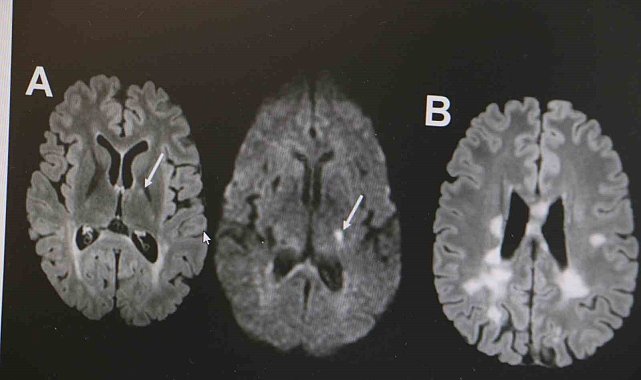

MS hastalığının kadın popülasyonunda daha sık görüldüğünün altını çizen Demir, "Kadınlarda erkeklere göre bu hastalık yaklaşık 2 kat daha sık görülmekte. MS hastalığı özellikle ataklarla seyreden bir hastalıktır. Hastaların yüzde 85'inde relapsing remitting form dediğimiz atak formuyla seyretmektedir. MS hastalığının tanısı klinik olarak kesin tanı konulabilse de günümüz şartlarında MR çekilmeden kesin tanı konulmaması önerilmektedir. MS hastalığının tedavisine gelecek olursak, kesin bir tedavisi yoktur. Ancak son 10 yılda çok sayıda ilaç kullanıma girmiştir. Bu açıdan MS hastalığı kontrol edilebilir bir hastalıktır. MS hastalığına bağlı ataklara karşı hastalara steroid tedavisi vermekteyiz. MS hastalarında görülen her şikayet atak olmayabilir. Özellikle idrar yolu enfeksiyonu, üst solunum yolu enfeksiyonu, aşırı egzersiz durumlarında, sıcak bir ortamda bulunma gibi durumda hastalarda ısı artışına bağlı olarak daha önceden var olan semptomlarda kötüleşme olabilir. Bunlar daha çok yalancı atak diyebiliriz. Ancak atak diyebilmemiz için şikayetin en az 24 saat sürmesi gerekmektedir" ifadelerinde bulundu.